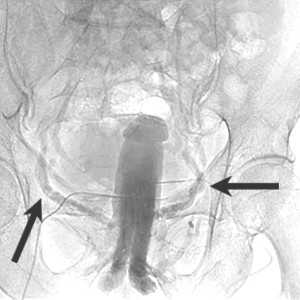

Кавернозография

Динамическая кавернозография - это диагностический тест, направленный на изучение причин веногенной эректильной дисфункции, и проводится при исключении других причин слабой потенции у молодых пациентов. Венозная утечка из эрегированного полового члена может развиться по разным причинам. Чаще всего это врождённое состояние или следствие тазовой венозной гипертензии (варикоцеле). При веногенной импотенции эрекция возникает, но она нестойкая, что не позволяет завершить половой акт. После выявления причин эректильной слабости у доктора появляется объект лечебного воздействия - несостоятельная вена, которую можно закрыть и улучшить эрекцию.

В процессе подготовки к выполнению кавернозографии сначала проводится измерение давления в пещеристых телах. В расслабленный пенис через инъекционный насос вводится 60 мл физиологического раствора + 20 мл контрастного препарата со скоростью 0,4 мл / с. Через 10 минут наступает эрекция полового члена. С целью визуализации заполнения кавернозных тел с боковых и прямых проекций после введения контраста выполняются рентгеновские снимки. При достижении интракавернозного давления в 150 мм.рт.ст. нагнетание раствора уменьшали до 0,1 мл в секунду для поддержания хорошей эрекции. При снижении артериального давления в пещеристых телах выполняли кавернозографию на фоне увеличения скорости инфузии.

Такой метод имитировал естественную эрекцию, а её ослабление в процессе исследования позволяло выявить наличие различных патологических венозных сбросов. Такая кавернозография даёт достаточно информации о венозных утечках, однако существует риск развития приапизма, а контрастирование дорсальной вены полового органа позволит определить эти утечки без необходимости интракавернозных инъекций. Однако прямая кавернозография необходима для выявления изменений органической структуры пениса при болезни Пейрони и разрывов в кавернозных телах.